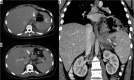

Purpose: The aim of study is to identify the frequency of acute complications and imaging findings at gastro-intestinal transit (GI) and computerised tomography (CT) in a group of obese patients who developed clinical suspicion of acute complications (painful and meteoric abdomen, nausea, vomiting, fever, intestinal blockage) in post bariatric surgery.

Material and methods: We retrospectively review 954 obese patients who underwent bariatric surgery between 2013 and 2019. The study included 72 patients who developed clinical suspicion of acute complications (painful and meteoric abdomen, nausea, vomiting, fever, intestinal blockage) within 6 days of bariatric surgery of sleeve gastrectomy, gastric banding, gastric bypass with Roux loop confirmed by CT, and who underwent a gastrointestinal transit before the CT examination.

Results: GI exam allowed visualisation of 58% of complications. Analysing the data for each surgical technique, 46 post-operative complications were found involve gastric banding. The most frequent was bandage migration (26 cases, 56 %), identified in all cases at GI transit and then confirmed on CT.